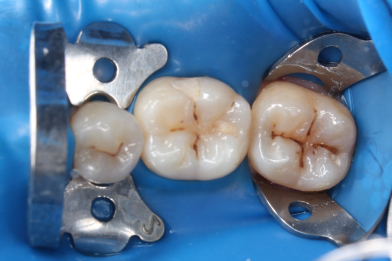

Для чего нужен КТ снимок? Не всегда можно увидеть кариес невооружённым взглядом. Данный

Бояринов Сергей Эдуардович

случай показывает наличие скрытого кариеса, который образовался на контактной поверхности

4.5 зуба. Именно наличие такого кариеса можно обнаружить при тщательной диагностике с

применением КТ снимка. -

Выполнена изоляция рабочего поля. Под инфильтрационной анестезией раствором Артикаина 1:100000 1,7 мл. Препарирование кариозной полости зуба. Пломба Ceram•X™ светового отверждения. Анатомическая форма зуба и целостность контактного пункта восстановлены

Бояринов Сергей Эдуардович -